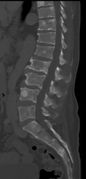

يُشخص المرض مخبريا بعمل عدة فحوصات و تشمل الفحوصات الوظيفية للكلية و قياس كمية الكالسيوم في الدم و عد مكونات الدم. و يستخدم الترحيل الكهربائي للبروتينات للتحري عن بعض البروتينات الغير طبيعية التي يتم إنتاجها بواسطة الخلايا السرطانية. للتحري عن أية كسور في العظام يتم تصوير المريض إشعاعيا بواسطة الجهاز الطبقي أو جهاز الرنين المغناطيسي.

CT scan of the lower vertebral column in a man with multiple myeloma, showing multiple osteoblastic lesions. These are more radiodense (brighter in this image) than the surrounding cancellous bone, in contrast to osteolytic lesions which are less radiodense.